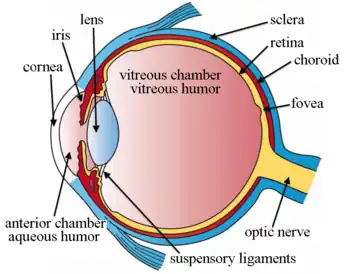

Right human eye cross-sectional view; eyes vary significantly among animals. | |

Additional images

The structures of the eye labeled